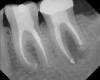

Figure 5  Retreatment of the case shown in Figure 4.

Figure 5